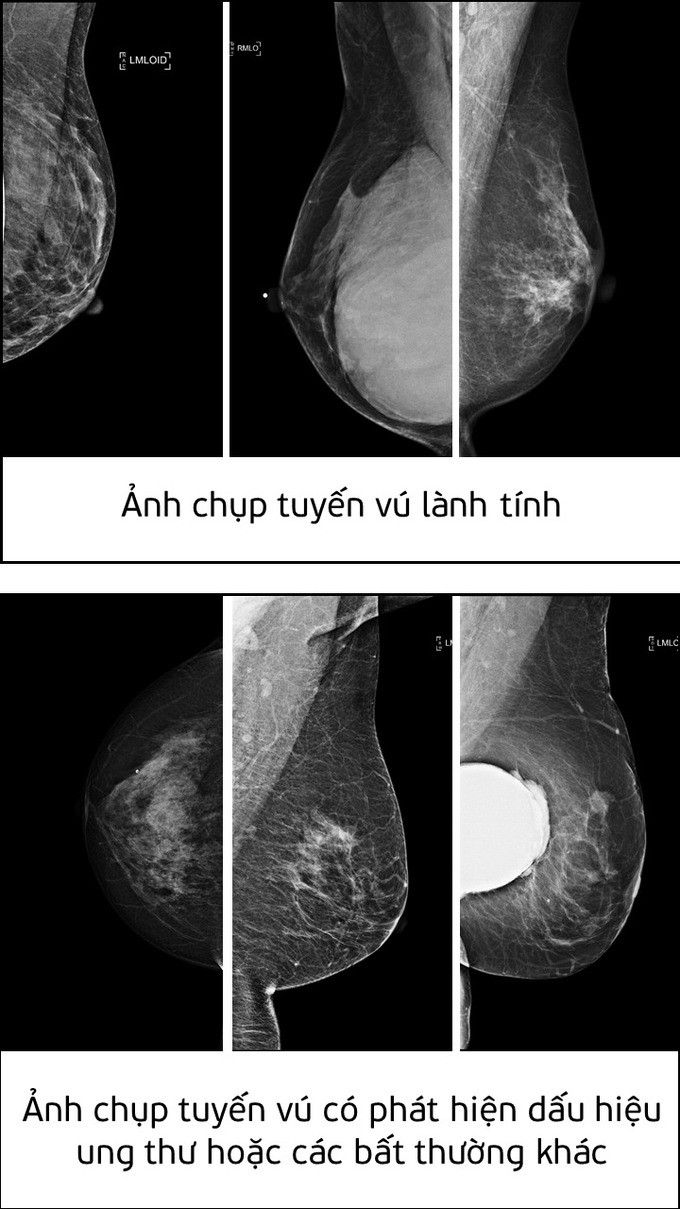

| Ảnh chụp tuyến vú lành tính và ảnh chụp tuyến vú có phát hiện dấu hiệu ung thư hoặc các bất thường khác. |